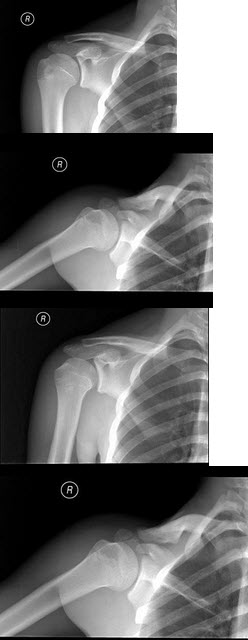

38、单项选择题

男,根据其正常肩关节影像图像,判断其最可能的年龄()

A.56岁左右

B.46岁左右

C.16岁左右

D.36岁左右

E.26岁左右